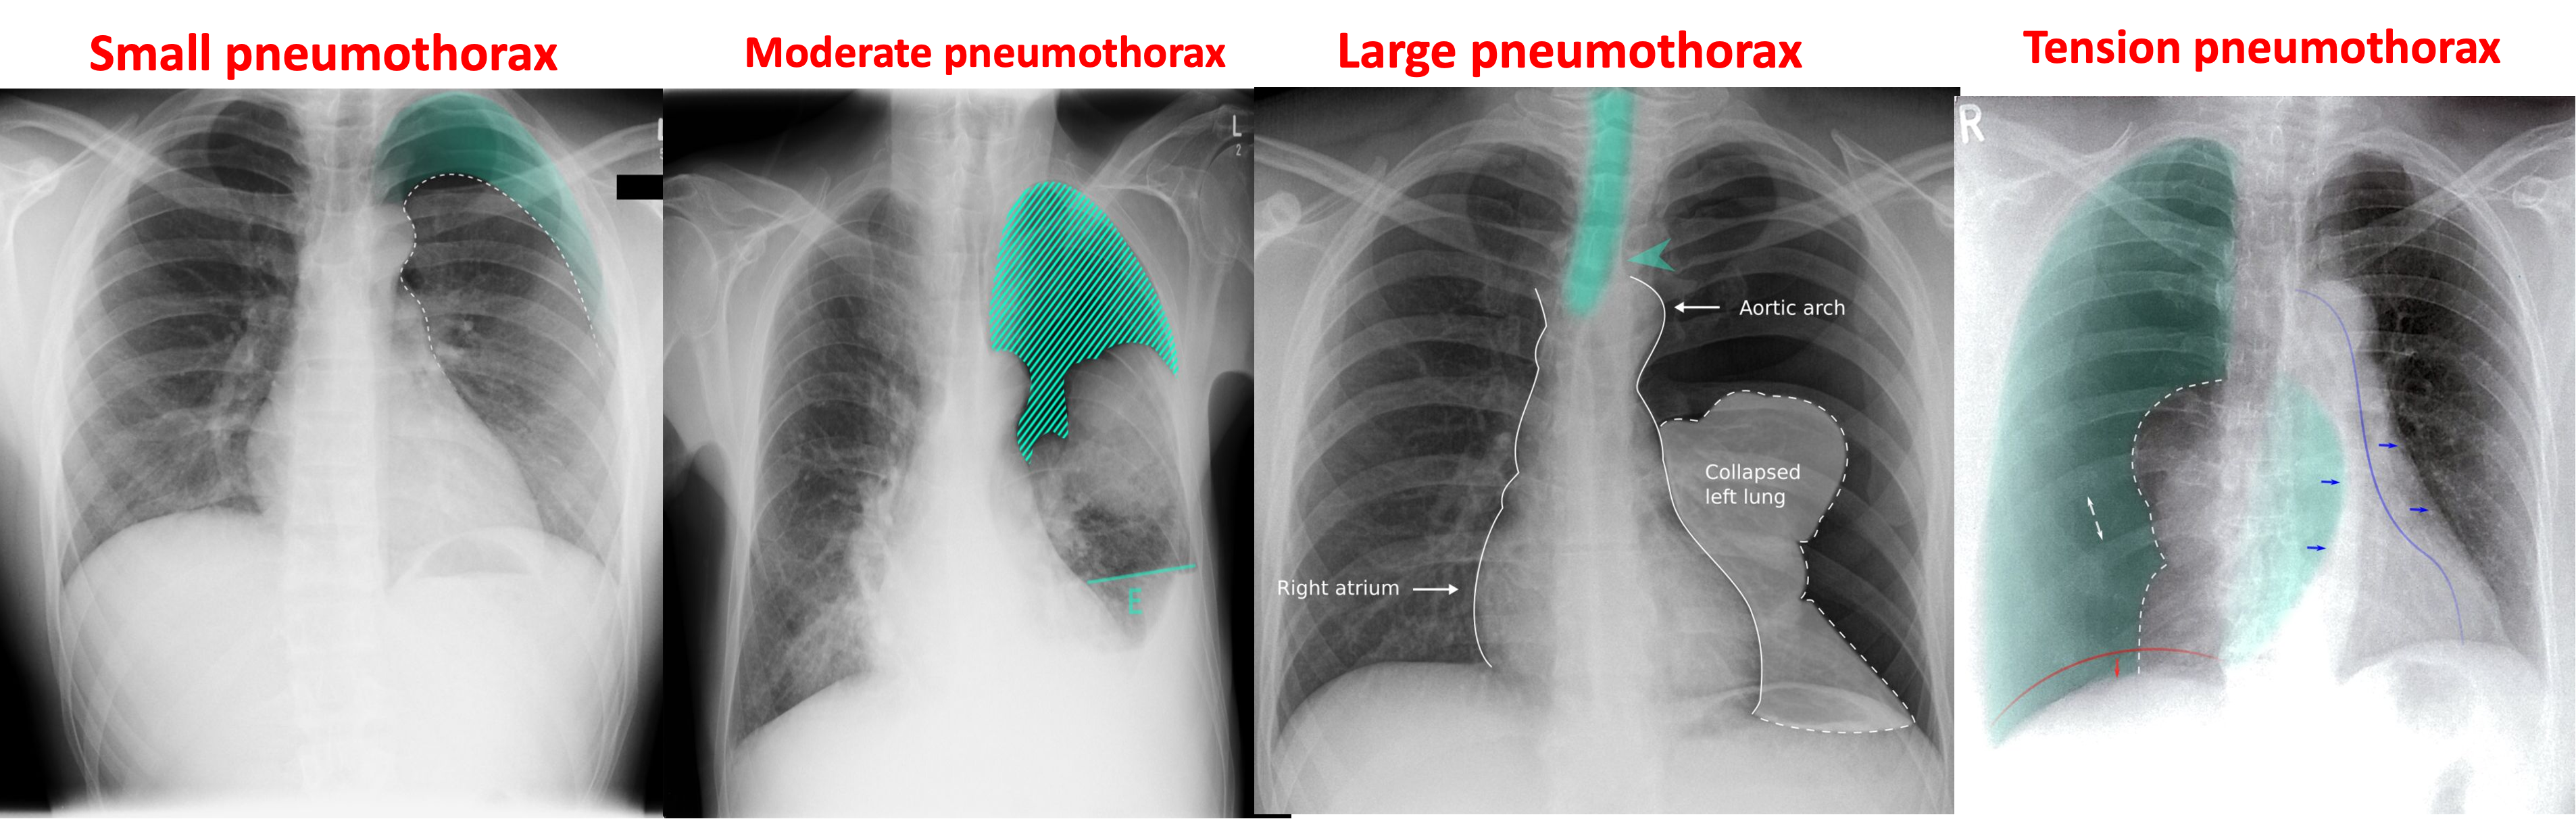

Small Pneumothorax:

< 20% of radiographic volume (best seen in expiratory film). Minimal symptoms.

Moderate Pneumothorax: When there is 20-50% of radiographic volume. Aspirate air.

Large Pneumothorax: When more than 50% of the radiographic volume and it causes shift of the trachea and mediastinum.

- Aspirate air.

Signs of pneumothorax

A) Supportive findings of pneumothorax

- Ipsilateral pleural line with reduced/ absent lung markings (i.e., increased transparency)

- Abrupt change in radiolucency

B) Supportive findings of Tension pneumothorax

- Ipsilateral diaphragmatic flattening/inversion and widened intercostal spaces.

- Mediastinal_shift toward the contralateral side.

- Tracheal_deviation toward the contralateral side.

Chest x-ray (PA view) Within the left lung, a thin convex line can be seen, beyond which there are no lung markings. Mediastinal structures are shifted to the contralateral side . Note the prominent tracheal deviation.